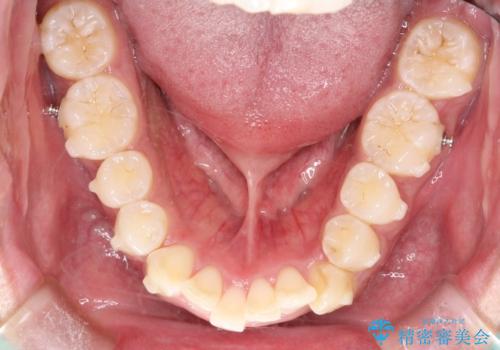

インビザラインによる出っ歯の矯正

- 出っ歯と下の歯のガタガタを主訴に来院されました。

上の奥歯を後方に移動させて、スペースを作り前歯を内側に引っ込める計画としました。

インビザラインによるマウスピース矯正で治療をすることとしました。

インビザラインをしっかり使用していただいたので、スムーズに治療をおえることができました。